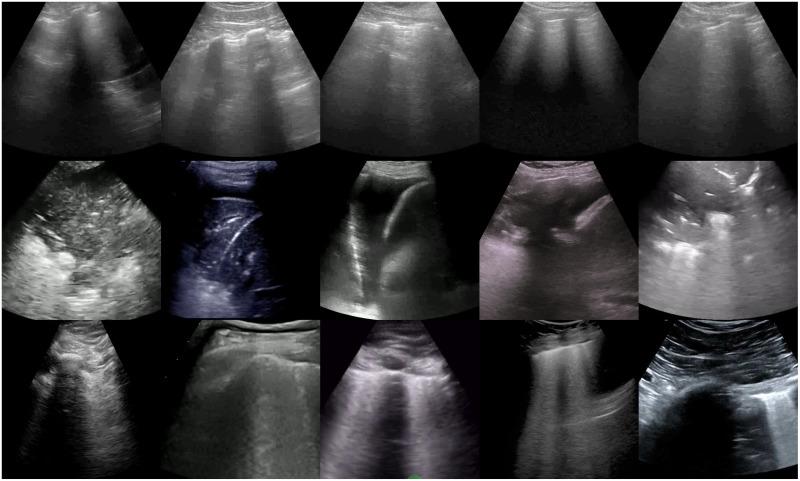

The COVID-19 pandemic has exposed the vulnerability of healthcare services worldwide, especially in underdeveloped countries. There is a clear need to develop novel computer-assisted diagnosis tools to provide rapid and cost-effective screening in places where massive traditional testing is not feasible. Lung ultrasound is a portable, easy to disinfect, low cost and non-invasive tool that can be used to identify lung diseases. Computer-assisted analysis of lung ultrasound imagery is a relatively recent approach that has shown great potential for diagnosing pulmonary conditions, being a viable alternative for screening and diagnosing COVID-19.

To evaluate and compare the performance of deep-learning techniques for detecting COVID-19 infections from lung ultrasound imagery.

We adapted different pre-trained deep learning architectures, including VGG19, InceptionV3, Xception, and ResNet50. We used the publicly available POCUS dataset comprising 3326 lung ultrasound frames of healthy, COVID-19, and pneumonia patients for training and fine-tuning. We conducted two experiments considering three classes (COVID-19, pneumonia, and healthy) and two classes (COVID-19 versus pneumonia and COVID-19 versus non-COVID-19) of predictive models. The obtained results were also compared with the POCOVID-net model. For performance evaluation, we calculated per-class classification metrics (Precision, Recall, and F1-score) and overall metrics (Accuracy, Balanced Accuracy, and Area Under the Receiver Operating Characteristic Curve). Lastly, we performed a statistical analysis of performance results using ANOVA and Friedman tests followed by post-hoc analysis using the Wilcoxon signed-rank test with the Holm's step-down correction.